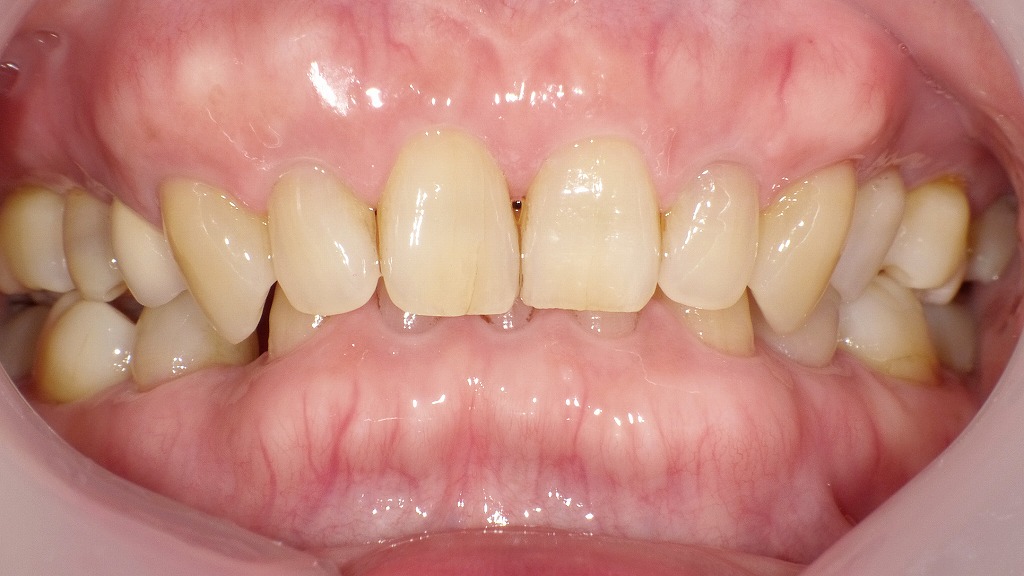

症例2:大人(永久歯)の過蓋咬合

この写真は、成人(永久歯列)における過蓋咬合(かがいこうごう)の口腔内を示しています。この画像でも、上の前歯が下の前歯を大きく覆っており、下の歯の見える部分がほとんどないことが確認できます。

👀 特徴

- 上の歯列が前方・下方に強くかぶさっている

- 下の前歯が上の歯ぐき(口蓋側粘膜)に接触しやすく、歯肉の損傷や炎症を起こす場合がある

- 奥歯の咬み合わせにも影響し、咬耗(すり減り)や顎関節症の原因になることがある